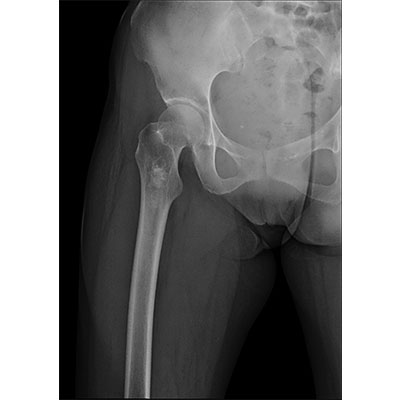

● 短曝光時(shí)間,便于老年人、兒童、殘疾人進(jìn)行臨床拍攝。避免這類(lèi)群體因不能有效控制身體運動(dòng)等因素造成的運動(dòng)偽影,提高攝片質(zhì)量及效率。